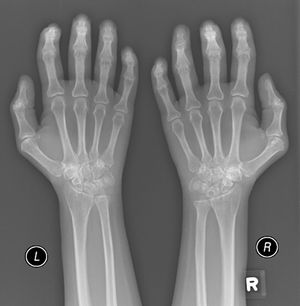

A 52-year-old male patient developed RA in March 2009 at the age of 43, with symmetric polyarthritis and active synovitis affecting hands, knees, ankles, and both feet without symptoms or signs suggestive of extra-articular features. Laboratory investigations in 2009 showed elevated markers of inflammation, negative rheumatoid factor and positive ant-CCP antibodies, negative ANA, negative anti-dsDNA antibodies; the plain X-rays of both hands showed typical erosive changes consistent with the diagnosis of RA mainly affecting the carpal bones with narrowed radio-carpal joints on both sides (Fig. 1). The patients fulfilled the ACR/EULAR (2010) classification criteria for RA.1 The patient showed much improvement on a combination therapy of disease-modifying antirheumatic drugs (DMARDs) including Methotrexate (MTX) 17.5mg/week/po, folic acid supplements, hydroxychloroquine (HCQ), and low dose of steroids (prednisolone 5mg/od/po). He had no symptoms or signs suggestive of any extra-articular features of the disease and no subcutaneous nodules, sicca symptoms or ILD. The patient showed marked improvement on the combination DMARDs and during the course of his disease he remained in remission without active synovitis or morning stiffness. He did well until January 2017 when he developed rapidly progressive shortness of breath with irrigative dry cough. On chest examination, there was bilateral infra-scapular inspiratory crepitations and high-resolution CT of the lung showed evidence of coarse reticular opacities and areas of consolidation consistent with ILD.

Plain X-ray both hands, showing cystic carpal bone erosions and decreased radio carpal joint space bilaterally, cystic erosions of the upper radius, carpo-metacarpal joints bone erosive changes and joint space narrowing of the proximal interphalangeal joints and metacarpophalangeal joints (MCP) with Juxta-articular osteoporosis.